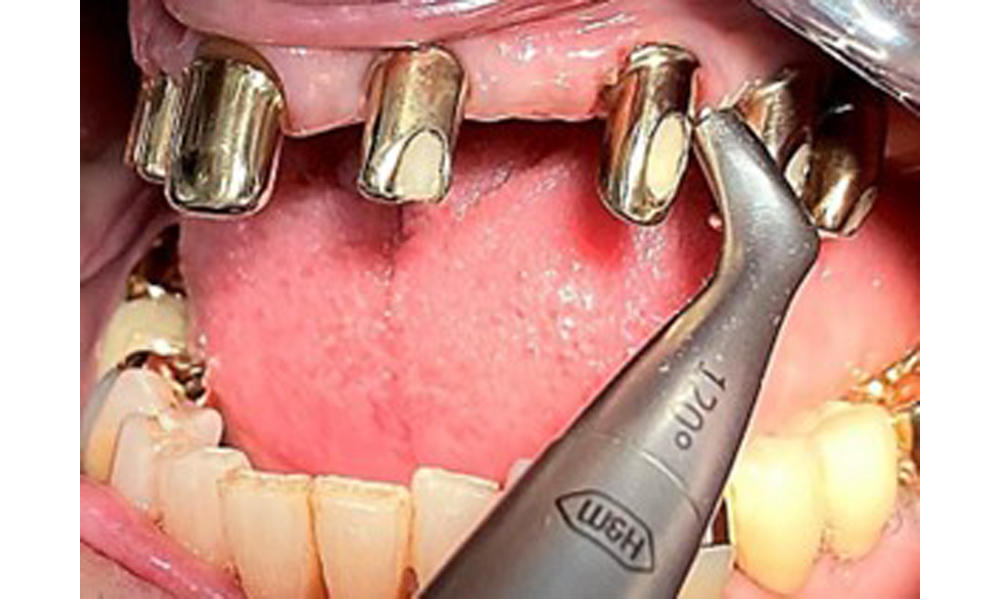

Die Patientin wurde vor über 25 Jahren mit einer kombinierten herausnehmbare Implantat-Teleskopprothese im Oberkiefer versorgt (Abb. 1, Abb. 2, Abb. 3) und ist sehr glücklich über ihren Zahnersatz. Im Unterkiefer hat die Patientin einen suffizienten festsitzenden Zahnersatz. (Abb. 4)

Frontalansicht mit dem eingesetzten Zahnersatz im Oberkiefer.

Abb. 1: Frontalansicht mit dem eingesetzten Zahnersatz im Oberkiefer.

Dentaler Befund

Der dentale Befund stellt sich wie folgt dar: Kombinierte herausnehmbare Implantat- und zahngetragene Teleskoparbeit auf Implantaten 15, 13, 21, 23, 24, 25 und Zahn 11 (Abb. 1, Abb. 2, Abb. 3). Im Unterkiefer ist die Patientin mit einem festsitzenden Zahnersatz versorgt. 37–34 sowie 45–47 haben suffiziente Brücken (Abb. 4). Kronenränder sind intakt, aktive kariöse Läsionen sind nicht vorhanden. An Zahn 43 zeigt sich eine Compositefüllung mit Randspalt. Im Unterkiefer liegen Rezessionen mit freiliegender Wurzeloberfläche zwischen 1 – 3 mm vor. Dies trifft auch für 11 zu.